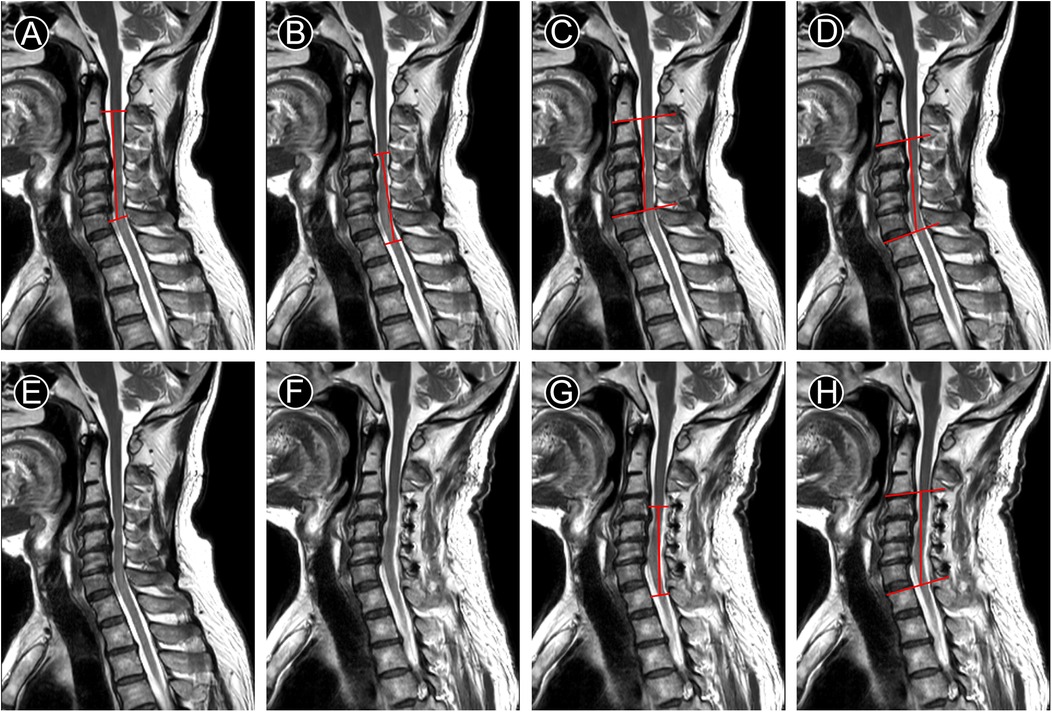

All the data above indicated that mK-line(+) and mSC-line(+) were both important for the segments selection of LAMP surgery and good prognosis. In a case of MCSM, we modified K-line(−) and SC-line Type III to mK-line(+) and mSC-line(+) respectively (Figures 3A–D). After LAMP surgery, patient's JOA score increased from 13–17, and who was completely recovered at 7-month follow-up. Widening of the spinal canal and relief of spinal cord compression were indirectly manifested by the clearly visualization of cerebrospinal fluid on postoperative T2-MRI (Figure 3F). The spinal cord shifted backward, whose indicators mK-INT and mSC-INT increased significantly (Figures 3G,H). This study analyzed the correlation between the neurological recovery rate with postoperative radiological indicators. The data suggested JOA score recovery rate (JOA-RR) was statistically correlated with both mK-INT and mSC-INT (Table 5).

Figure 3

Figure 3. T2-MRI of a case with MCSM underwent LAMP for C4–C7. (A–D) preoperative measurement line. (G–H) postoperative measurement line. A. K-line(−), (B) mK-line(+), (C) SC-line Type III, (D) mSC-line(+), (E) preoperative image shows obstructed cerebrospinal fluid, (F) Image at 7 months after operation shows unobstructed cerebrospinal fluid, (G,H) mK-INT and mSC-INT increased.